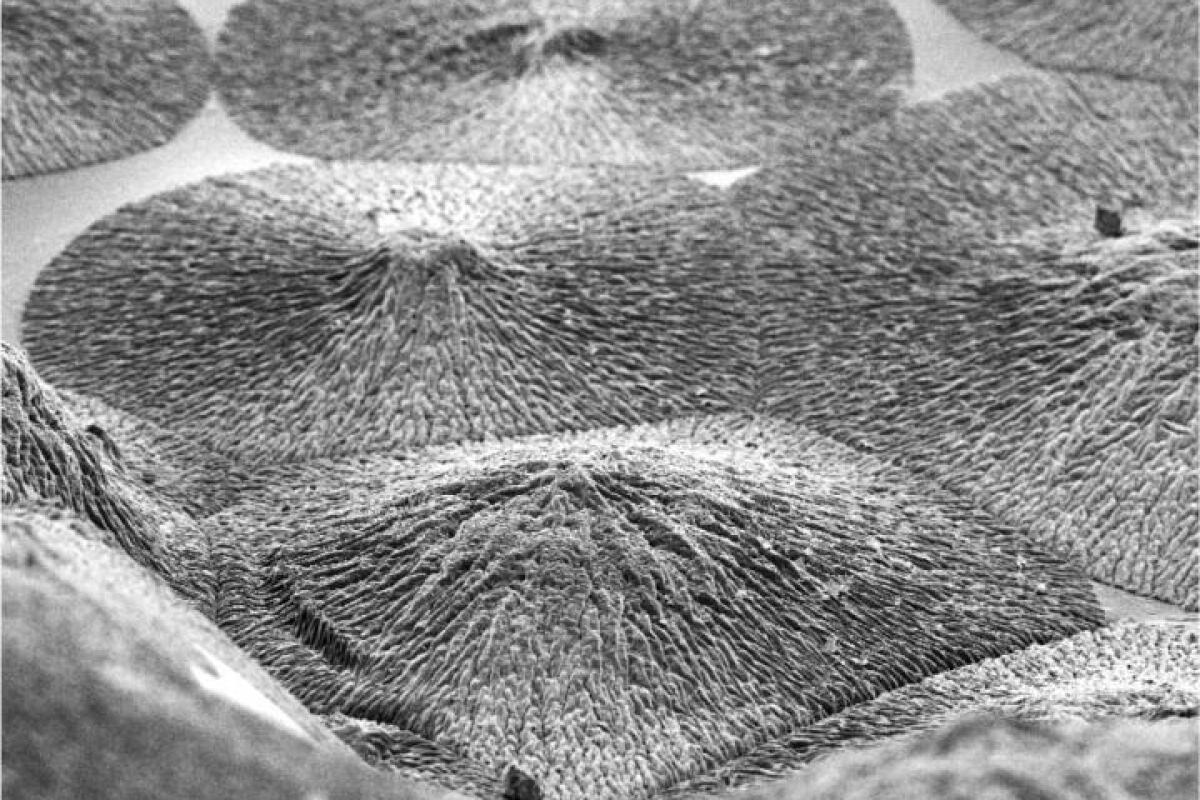

From newatlas.com

New approach could grow materials that exactly mimic bone or dental enamel What Is Enamel Material  Covering steel elements with enamel. This video and article are an introduction to the material of vitreous enamel itself, which metals can be enamelled, what reactions we can expect when. It is a durable and versatile material. Enamel paint is frequently used for painting walls, trim, and other surfaces in both interior and exterior settings. Enamel paint can be applied. What Is Enamel Material.